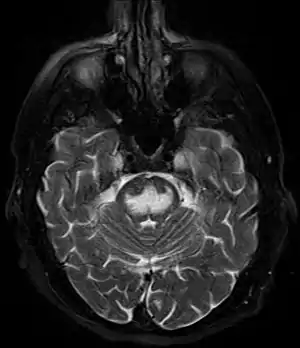

| Axial fat-saturated T2-weighted image showing hyperintensity in the pons with sparing of the peripheral fibers, the patient was an alcoholic admitted with a serum Na of 101 treated with hypertonic saline, he was left with quadriparesis, dysarthria, and altered mental status | |

It can be diagnosed clinically in the appropriate context, but may be difficult to confirm radiologically using conventional imaging techniques. Changes are more prominent on MRI than on CT, but often take days or weeks after acute symptom onset to develop. Imaging by MRI typically demonstrates areas of hyperintensity on T2-weighted images.[29]